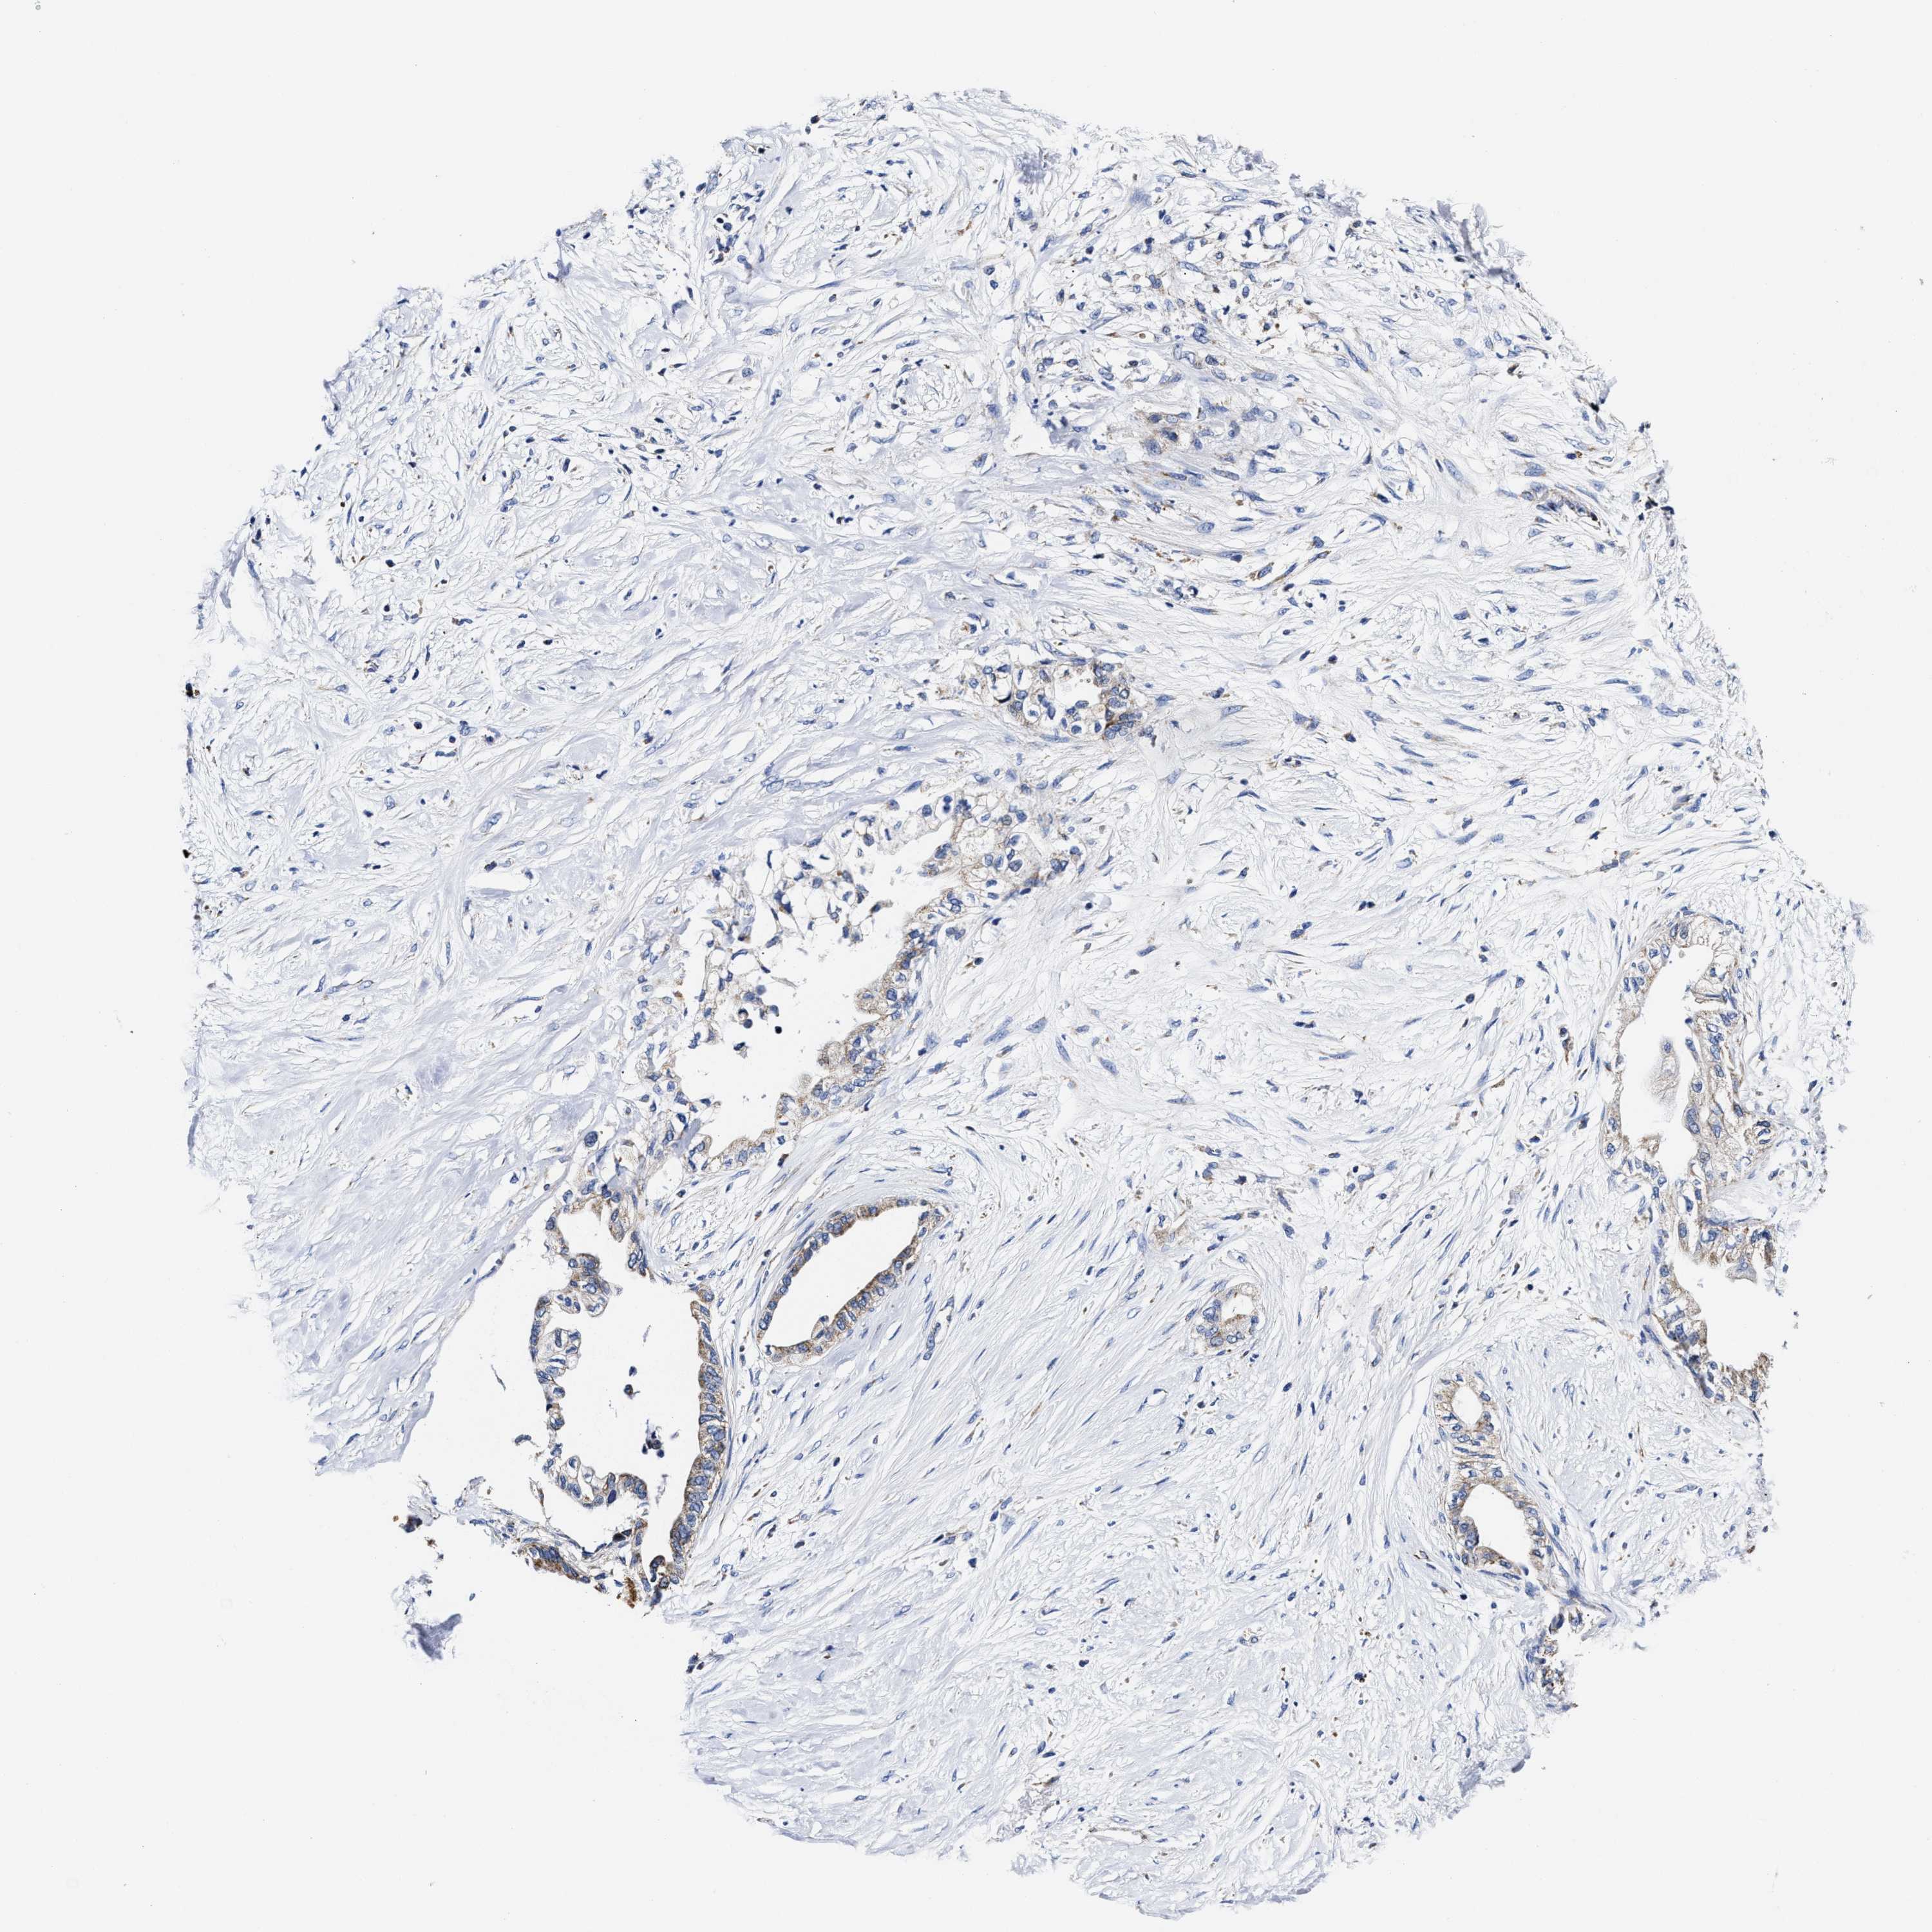

PANCREATIC CANCER - Protein expressioni

A mouse-over function shows sample information and annotation data. Click on an image to view it in a full screen mode. Samples can be filtered based on level of antibody staining by selecting one or several of the following categories: high, medium, low and not detected. The assay and annotation is described here.

Note that samples used for immunohistochemistry by the Human Protein Atlas do not correspond to samples in the TCGA dataset.

Antibody stainingi

Antibody staining in the annotated cell types in the current human tissue is reported as not detected, low, medium, or high, based on conventional immunohistochemistry profiling in selected tissues. This score is based on the combination of the staining intensity and fraction of stained cells.

Each image is clickable and will lead to virtual microscopy that enables deeper exploration of all samples and also displays staining intensity scores, fraction scores and subcellular localization as well as patient and tissue information for each sample.

Antibody HPA020961

Antibody HPA059109

Staining

High

Medium

Low

Not detected

Intensity

Strong

Moderate

Weak

Negative

Quantity

>75%

75%-25%

<25%

None

Location

Nuclear

Cytoplasmic/membranous

Cytoplasmic/membranous,nuclear

Adenocarcinoma, NOS